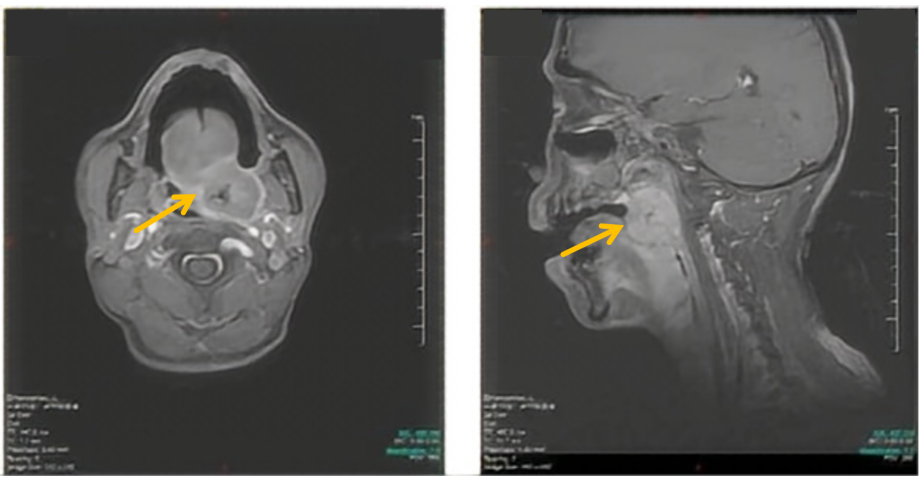

口咽MRI平扫+增强(2023-4-25):1.会厌劈裂、口咽左侧壁、舌根部见T1WI稍低信号,T2WI及DWI稍高信号不规则肿块影,病灶大小4.3cm×2.6cm×7.3cm,侵犯左侧软腭;2.左颈部见数枚T1WI稍低信号、T2WI及DWI稍高信号结节,大者大小约2.0cm×1.6cm,转移瘤可能。

图1 患者口咽部MRI表现

左侧口咽、舌根活检(2023-4-25):(口咽、舌根)结外NK/T细胞淋巴瘤,鼻型。EBER原位杂交(+),Ki-67(+70%),CD3(+),TIA-1(+),LCA(+),CD56(+),CD43(+),CD2(+),CD8(+),Mum-1(+),Bcl-2(+),Pax-5(-),CD20(-),CD10(-),Bcl-6(-),CD4(少量+),CD30(-),CK广谱(-),p40(-),P63(-),P16(-),EGFR(-),34βE-12(-)。